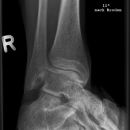

Sprunggelenk a.p.

Freier Einblick in den kompletten Gelenkspalt? (Aufnahme in 15-20° Innenrotation, beide Malleolen in gleicher Tischplattenentfernung!) -> Kontur der Incisura fibularis tibiae und laterale Talusrollenkontur in einer Fluchtlinie?

Beurteilungskriterien

• Weite (lateral 4-5mm, medial 3-4mm) und Kongruenz des Gelenkspalts

• Syndesmosenspalt < 5mm

• Fluchtlinie von Incisura fibularis und lateraler Talusrollenkontur -> Versetzung weist auf (osteo-)ligamentäre Verletzung hin!

• tibiofibulare Gelenkkontur

• Weichteilschwellung (v.a. ventral des Gelenkspaltes in der seitlichen Aufnahme und um den lateralen Malleolus in der ap.-Projektion)

• Target areas häufiger subtiler Frakturlokalisationen:

• Kontur der Malleolen und Malleolarspitzen

• posterolaterale Tibiakantenabscherungen (Volkmann-Dreieck)

• Kanten der Trochlea tali (Flake-Frakturen bei bis zu 7% der OSG-Distorsionen!)

• Talushals, Processus lateralis

• Cave : akzessorische Knochen (Os trigonum, Os supratalare, Os supranaviculare, Os tibiale externum)